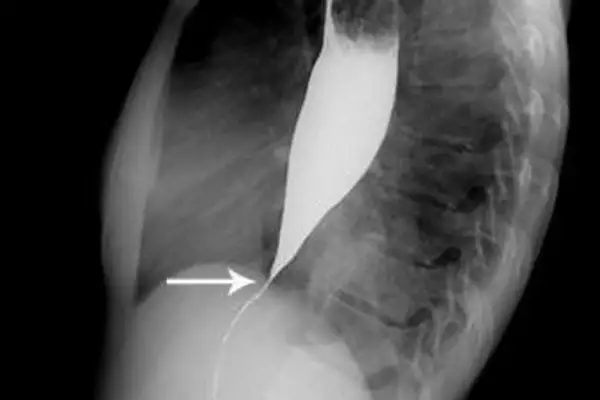

- рентгенологическое контрастное исследование – пациенту предлагают проглотить порцию контрастного вещества (сульфата бария), после этого делают серию рентгенологических снимков. По ним выявляют скорость перемещения сульфата бария по пищеводу и освобождения от него конечного участка пищевода;

- Рентгенография грудной клетки. Обследование начинается именно с данного исследования. В случае выявления на рентгенограмме тени расширенного пищевода с жидкостным уровнем назначается рентгенография пищевода, предполагающая предварительный прием бариевой взвеси. Если имеет место ахалазия кардии, то становится заметным сужение конечного отдела пищевода, а также расширение участка, располагающегося выше.

Рентгенологическими признаками кардиоспазма являются расширение пищевода в той или иной степени с наличием «узкого сегмента» в терминальном его отделе. Стенки пищевода, в том числе и в суженной части, сохраняют эластичность. В расширенном пищеводе натощак определяется значительное количество жидкости.